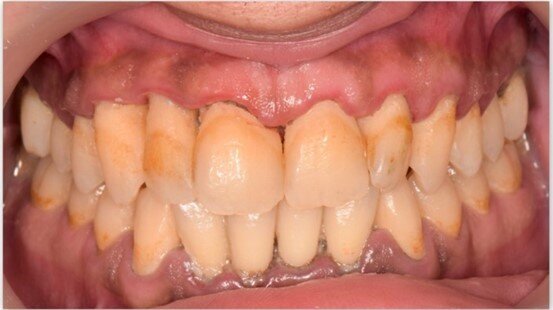

A una settimana dall’applicazione, i pazienti riferiscono una riduzione significativa di sanguinamento e sensibilità gengivale, con risultati superiori rispetto alla sola pulizia professionale. Nei casi di gengivite e tasche parodontali fino a 3 mm, UBIGEL INPERIO ha dimostrato di favorire una parziale o completa regressione dell’infiammazione, contribuendo al ripristino dell’attacco epiteliale e all’eliminazione del sanguinamento grazie alla sua azione antibatterica mirata. Nella Figura 1 è mostrata la situazione iniziale del paziente prima del trattamento.Dopo una settimana dall’applicazione di Ubigel Inperio (Fig. 2), si osservano i primi miglioramenti clinici. Il sondaggio pre-trattamento, effettuato sette giorni dopo l’igiene professionale, evidenziava una profondità di 3 mm con presenza di sanguinamento gengivale (Fig. 3). A distanza di 21 giorni dal trattamento, il sondaggio mostra una profondità della tasca inferiore a 2 mm e l’assenza di sanguinamento, segno di un netto miglioramento dello stato gengivale (Fig. 4).